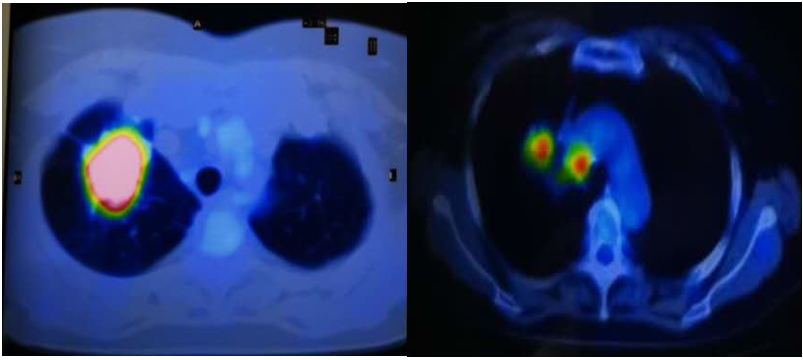

治疗前基线:右肺上叶多发结节,大者(2.3*2.0*2.1cm)考虑恶性。

治疗2月后:(SD)右肺上叶多发结节,大者(2.0*1.5*1.8cm)恶性可能性大。

治疗8月后:(PR)右肺上叶多发结节,大者(1.2*1.1cm)较前明显缩小。

治疗13个月后(2021-8):(PR)